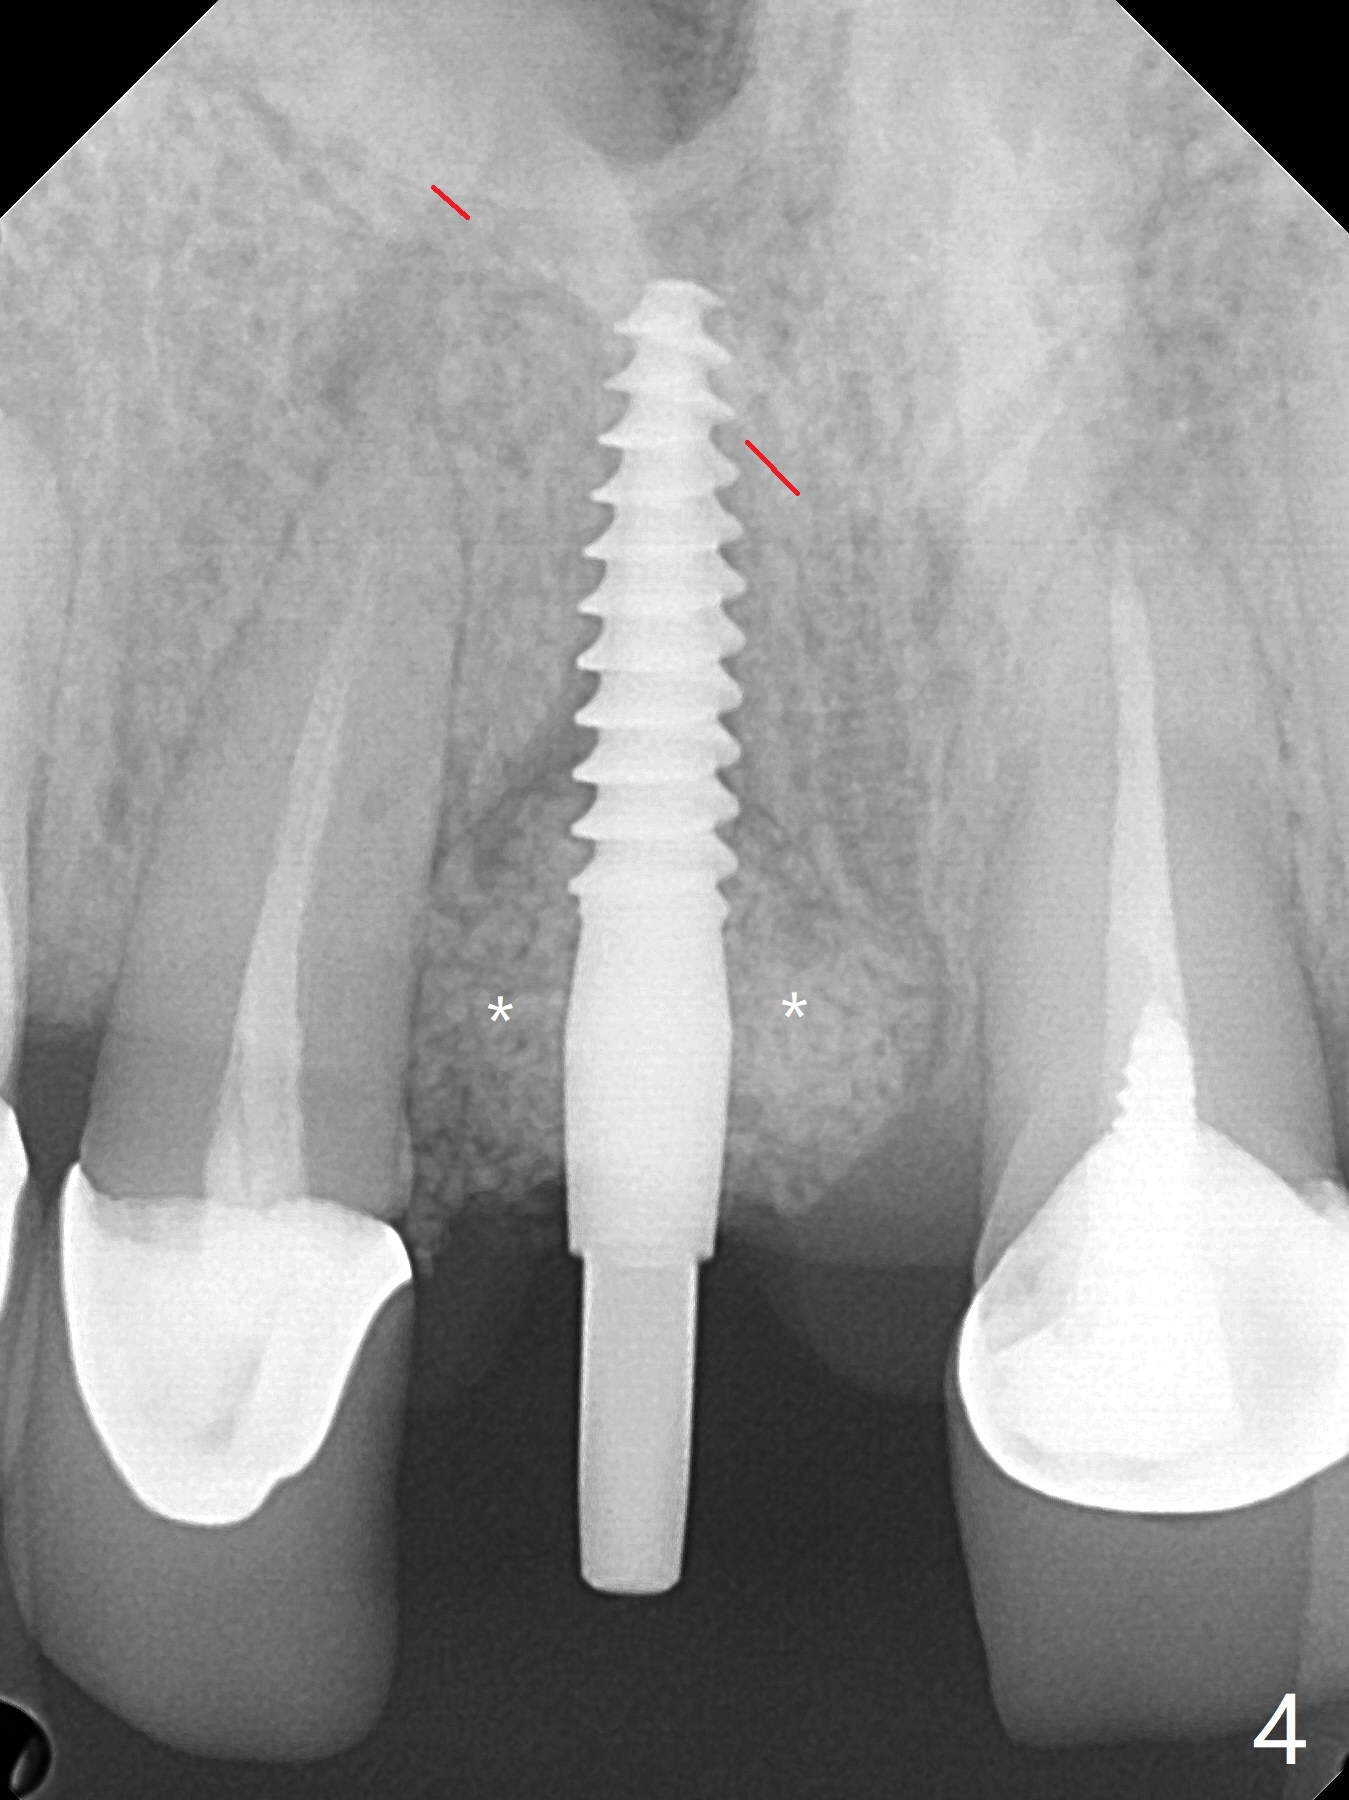

徒手初步钻洞显示方位不对(图一),重新钻洞方位尚可,好像接近鼻底(图二:红线);植入3x11.5毫米一段式植体(图三),3-5个螺纹暴露,植体似乎接近鼻底;旋转植体三趟,植体仿佛卡人鼻底,扭力大约35Ncm,植入粘性骨粉(图四,五:*)前,塞入PRF膜,紧贴颊侧粘膜,促进瘘道愈合。骨粉不仅围绕植体,而且紧贴邻牙牙根(图六(第二轮植骨:overgrafting):<)。病人术后第二周开始使用水牙线,术后三周牙龈健康多了,瘘道消失(图七)。术后六周颊侧骨壁开始塌陷(图八:>),临时牙冠颊侧颈部显得隆起(*)。调整后,牙冠外形改善(图十一至十三),取模前颊侧牙龈缘有可能下降,两个中切牙龈缘可能一致。术后3.5个月骨粉形态(图十四)与术后即刻(图六)有所不同。颊侧牙龈仍红肿轻度触痛(图十五),可能因为临时牙冠不利于局部卫生,所以决定取模制作永久性牙冠。粘固时使用临时胶水,并且涂抗菌素。另外一个可能因素是颊侧骨板薄(图十六:*),细菌感染植体螺纹,永久性牙冠粘固前,拍摄CT(放置cotton roll),必要时,植骨。永久性牙冠远中有缝隙,为了预防病人后悔,使用临时性粘固剂固定(图十七)。Return to No Caries DIO 下一个病例 一段式植体边缘制备 导板与内提升 Xin Wei, DDS, PhD, MS 1st edition 12/22/2020, last revision 06/15/2021